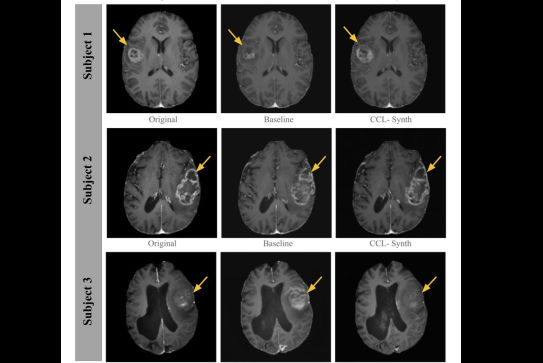

AI models can generate synthetic equivalents to PET images from routinely acquired T1W MRI scans.Louise Baron and ISMRM